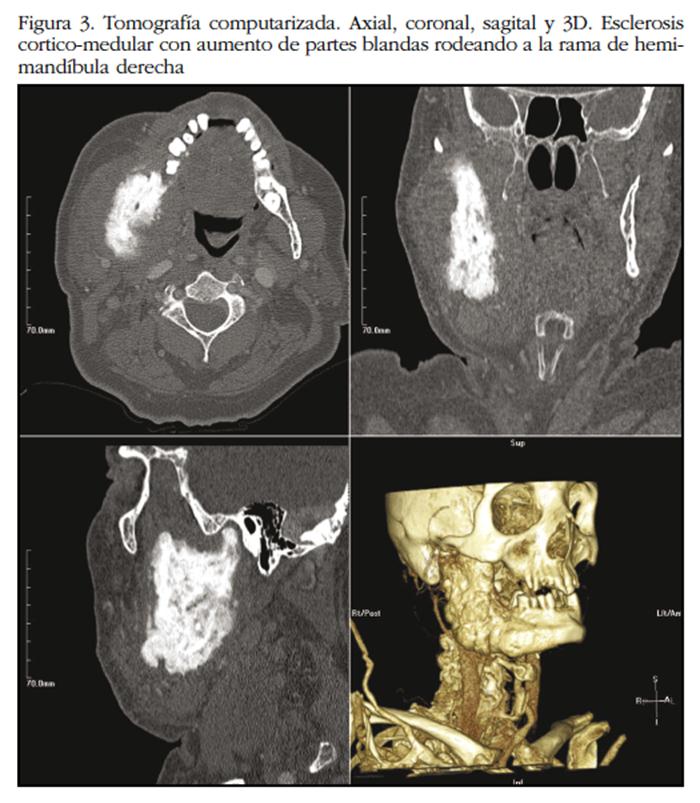

No recibe tratamiento por estabilidad sintomática hasta 11 meses ulteriores, cuando la clínica maxilofacial se acentúa. Radiológicamente se evidencia intensificación de la esclerosis con crecimiento óseo mandibular, aumento de partes blandas en espacio masticador, además de adenopatías en niveles Ia y Ib cervicales derechos (Figura 3). Una nueva biopsia submucosa de tejidos blandos y ósea, informa de tejido fibroso con cambios de esclerosis e intenso artefacto, con infiltración por células malignas de aspecto epitelial positivas para CK, AE1/AE3 y PSA. Además, es diagnosticado de una nueva metástasis ósea a nivel de pala ilíaca izquierda. Se desestima quimioterapia, y se aplican sendas dosis de 20 Gy de radioterapia con intención antiálgica en mandíbula y pelvis.